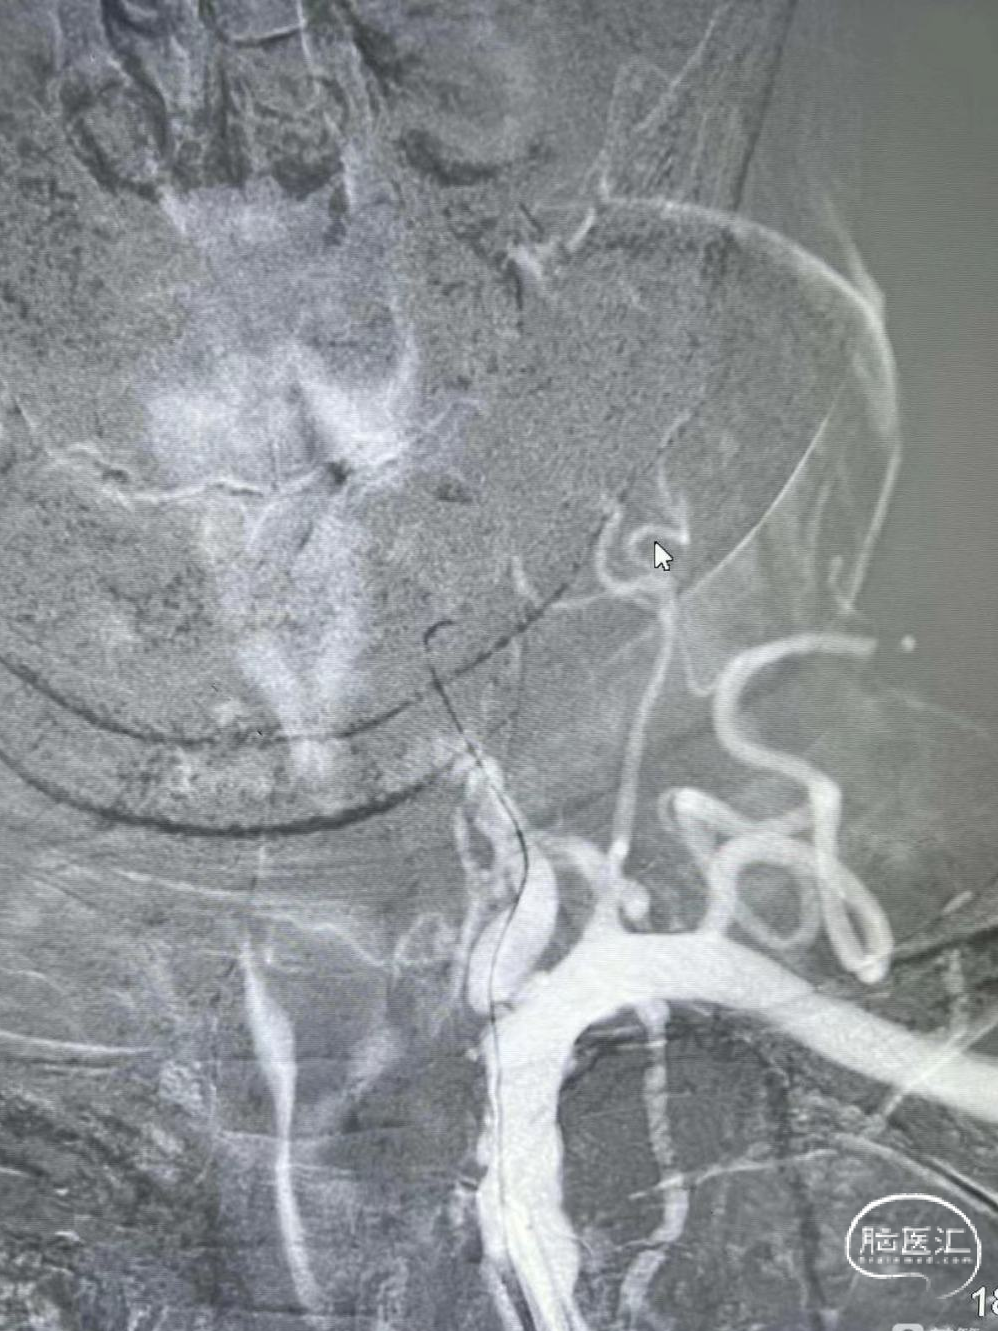

支架释放:

释放4mm*25mm Neurohawk取栓支架,可见支架显影良好,支撑性好,远端打开良好。中间导管跟上抽吸-SWIM技术。

操作要点:

固定支架推送杆,缓慢回撤支架微导管。

4

支架回撤:

借助支架锚定,跟进中间导管至接触血栓,SWIM技术取栓一次,恢复血流。